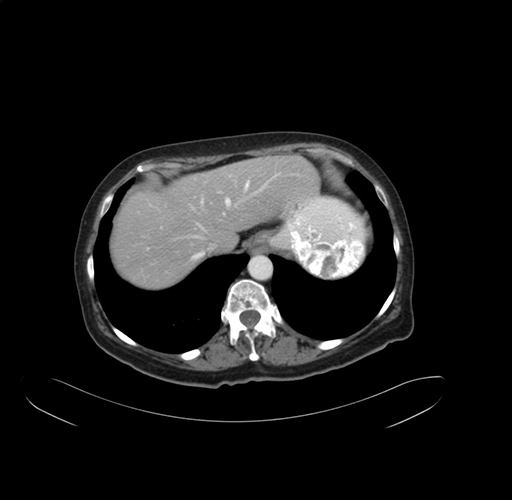

Pre-Chemo: Axial Venous

Axial Venous

Imaging analysis

Based on your CT findings, which issue(s) would give reason for "planned slowing down moment(s)" in this case?

Considering a standard right hepatectomy procedure, what step(s) of the operation would you do differently in this case?